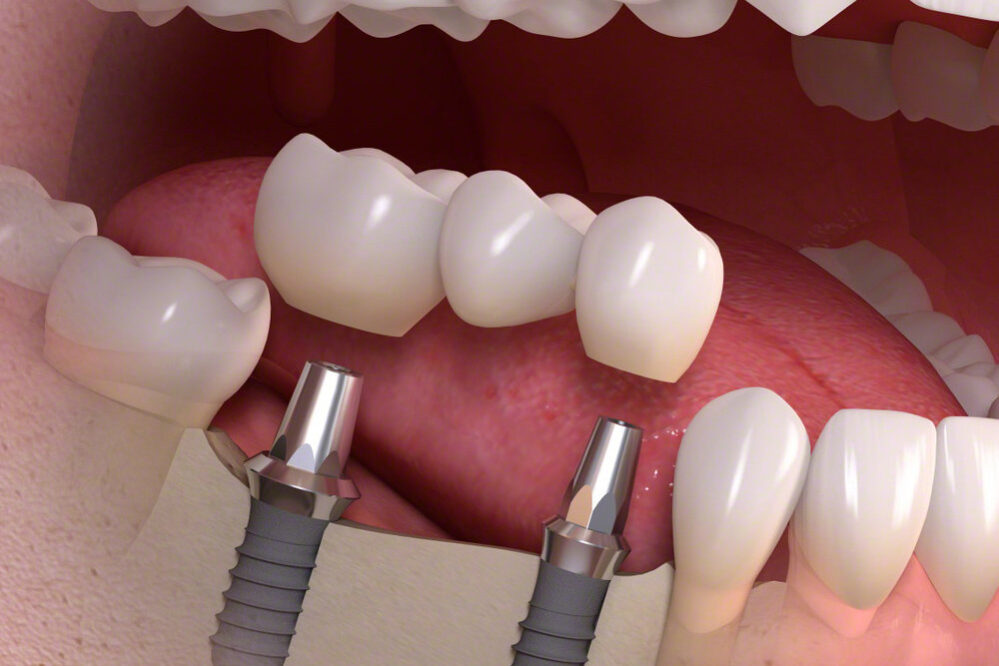

Los implantes dentales son la mejor solución para la reposición permanente de los dientes ausentes.

El tratamiento con implantes evita tener que rebajar dientes naturales, olvidándonos de llevar prótesis removibles, ganando en comodidad y volviendo a la percepción de volver a tener dientes naturales.

En Clínica Dental Marín empleamos implantes de alta gama, trabajamos con implantes Straumann®, ya que sólo los mejores materiales garantizan resultados únicos y duraderos.